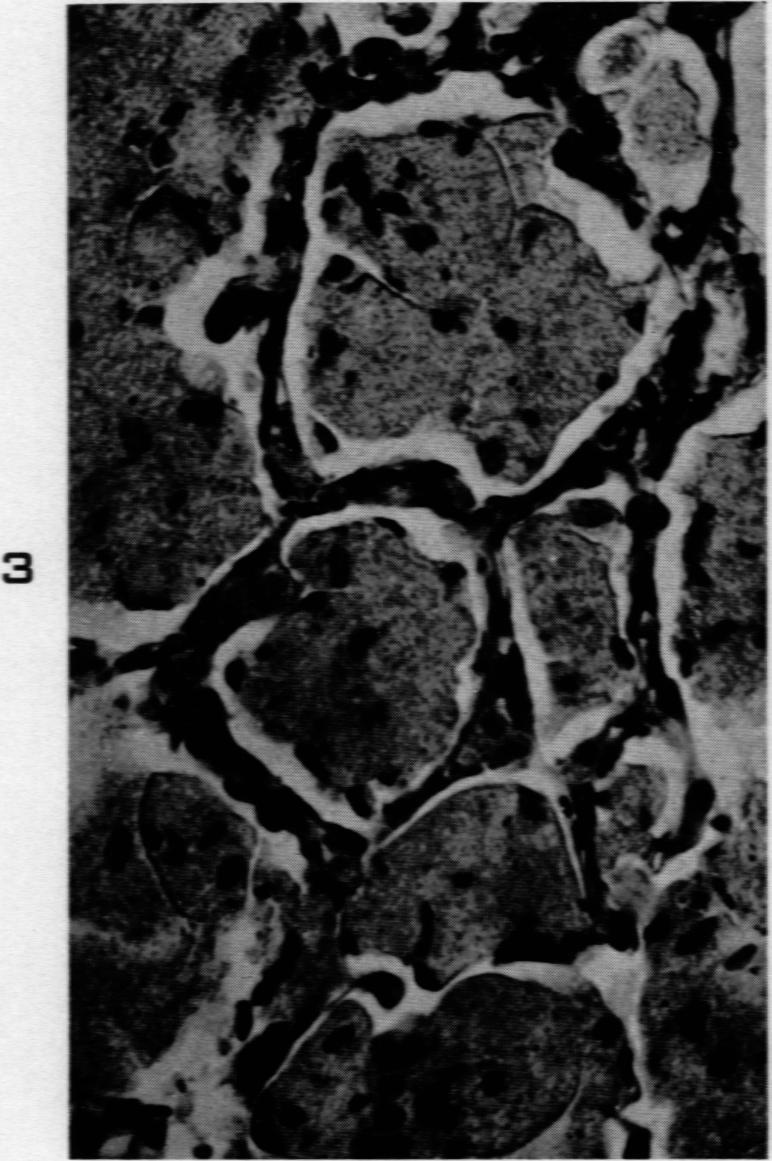

SCHEPERS G W

Am J Pathol. 1959 Nov-Dec;35(6):1169-87.